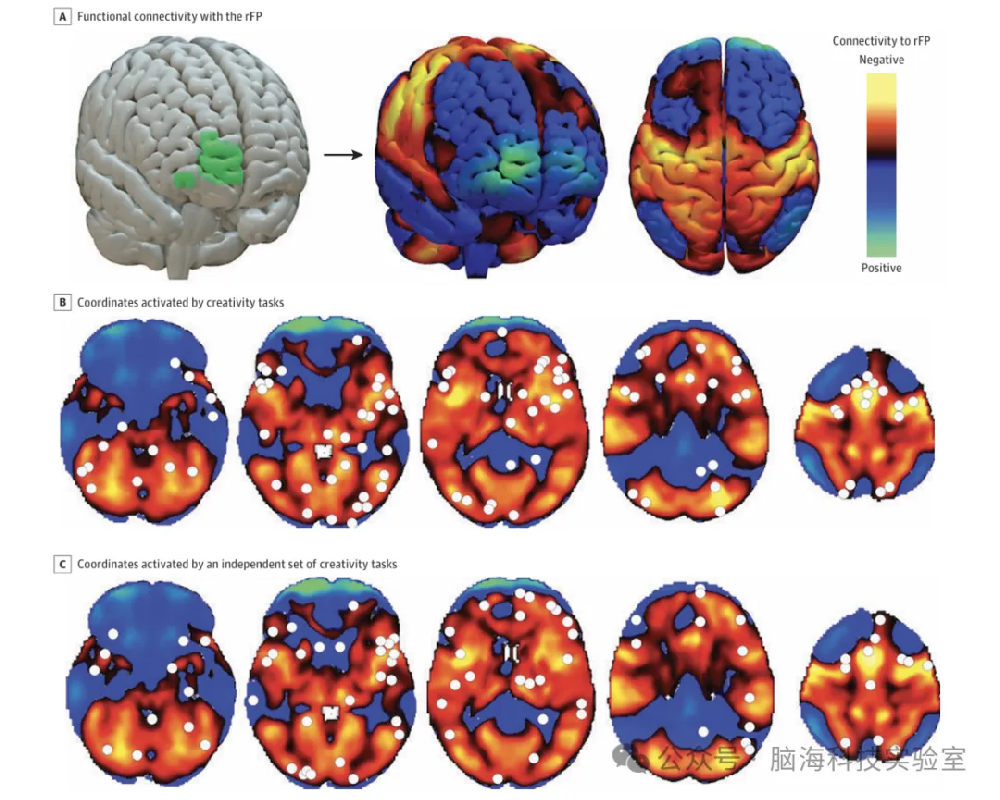

多模态脑影像数据分析平台